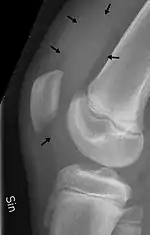

X-ray of the knee of a 12-year-old male, with knee effusion extending into the suprapatellar bursa.

- the suprapatellar bursa or recess between the anterior surface of the lower part of the femur and the deep surface of the quadriceps femoris.[2] It allows for movement of the quadriceps tendon over the distal end of the femur. In about 85% of individuals, this bursa communicates with the knee joint. A distension of this bursa is therefore generally an indication of knee effusion.[3]